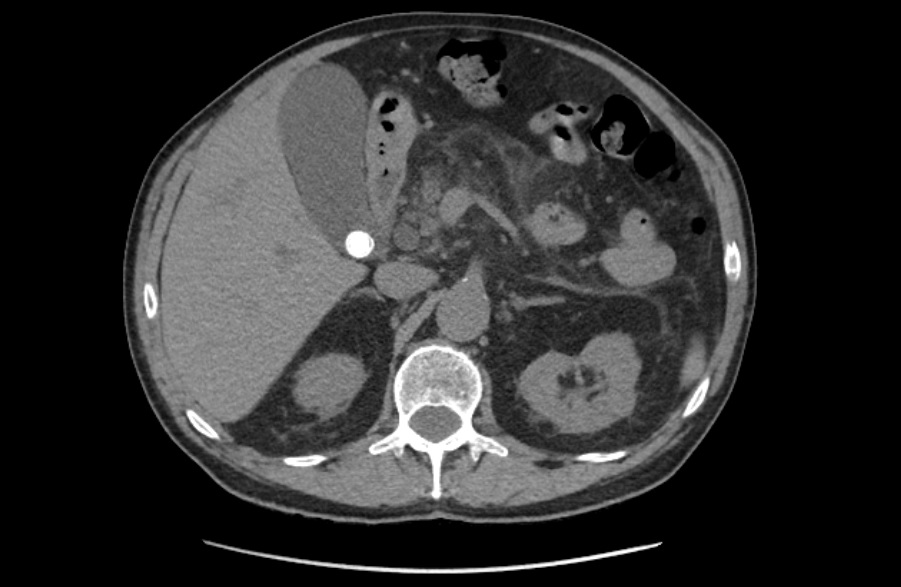

La litiasis y la dilatación de la vesícula biliar encontrada en la ecografía clínica no justificaba todo el cuadro, por lo que solicitamos ecografía reglada al equipo de radiología. En ella informan marcada dilatación de la vía biliar intrahepática, con un colédoco de hasta 15 mm, y estructura mamelonada de aproximadamente 7 cm en cabeza pancreática. Se completa estudio con Tomografía Axial Computarizada que confirma masa en cabeza pancreática compatible con adenocarcinoma que condiciona dilatación de la vía biliar retrógrada.